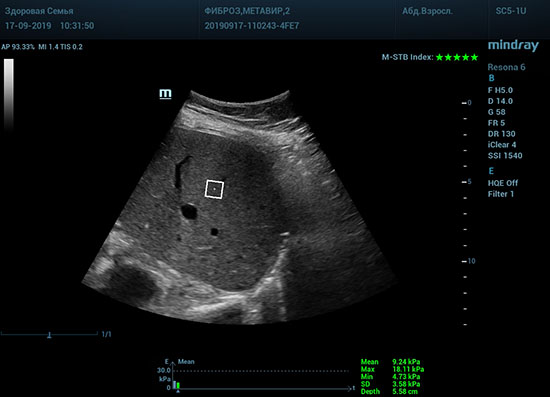

Определение плотности печени. Не ошибся ли оператор при измерении эластических свойств печени? Для оценки критериев качества предусмотрен индекс MBT, который покажет насколько «твердой» была рука оператора и двигалась ли печень. При MBT 5* рука тверда и показатели достоверны. Для оценки качества результатов используется IQR индекс, отображающий колебания показателей в точке измерения при расчете медианы. Показатели при IQR <30% считаются приемлемыми. Техника сканирования через межреберные промежутки требует размещение окна интереса на несколько сантиметром ниже капсулы, для исключения эффекта реверберации. Установка ROI на паренхиму без захвата сосудов, для исключения погрешностей измерения.

Стадия фиброза определяется по системе METAVIR Staging, построенной на данных биопсии и сопоставлении с данными эластографии. Своевременная диагностика фиброза, и начало его лечения, залог благоприятного исхода заболевания.